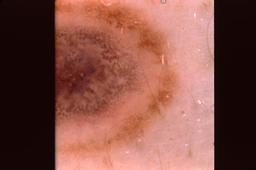

{

"age_approx": 50,

"anatom_site_general": "posterior torso",

"concomitant_biopsy": true,

"dermoscopic_type": "contact non-polarized",

"diagnosis_1": "Benign",

"diagnosis_2": "Benign melanocytic proliferations",

"diagnosis_3": "Nevus",

"diagnosis_4": "Nevus, Atypical, Dysplastic, or Clark",

"diagnosis_5": "Nevus, Dysplastic",

"diagnosis_confirm_type": "histopathology",

"image_type": "dermoscopic",

"lesion_id": "IL_8277002",

"melanocytic": true,

"patient_id": "IP_0549781",

"sex": "male"

}